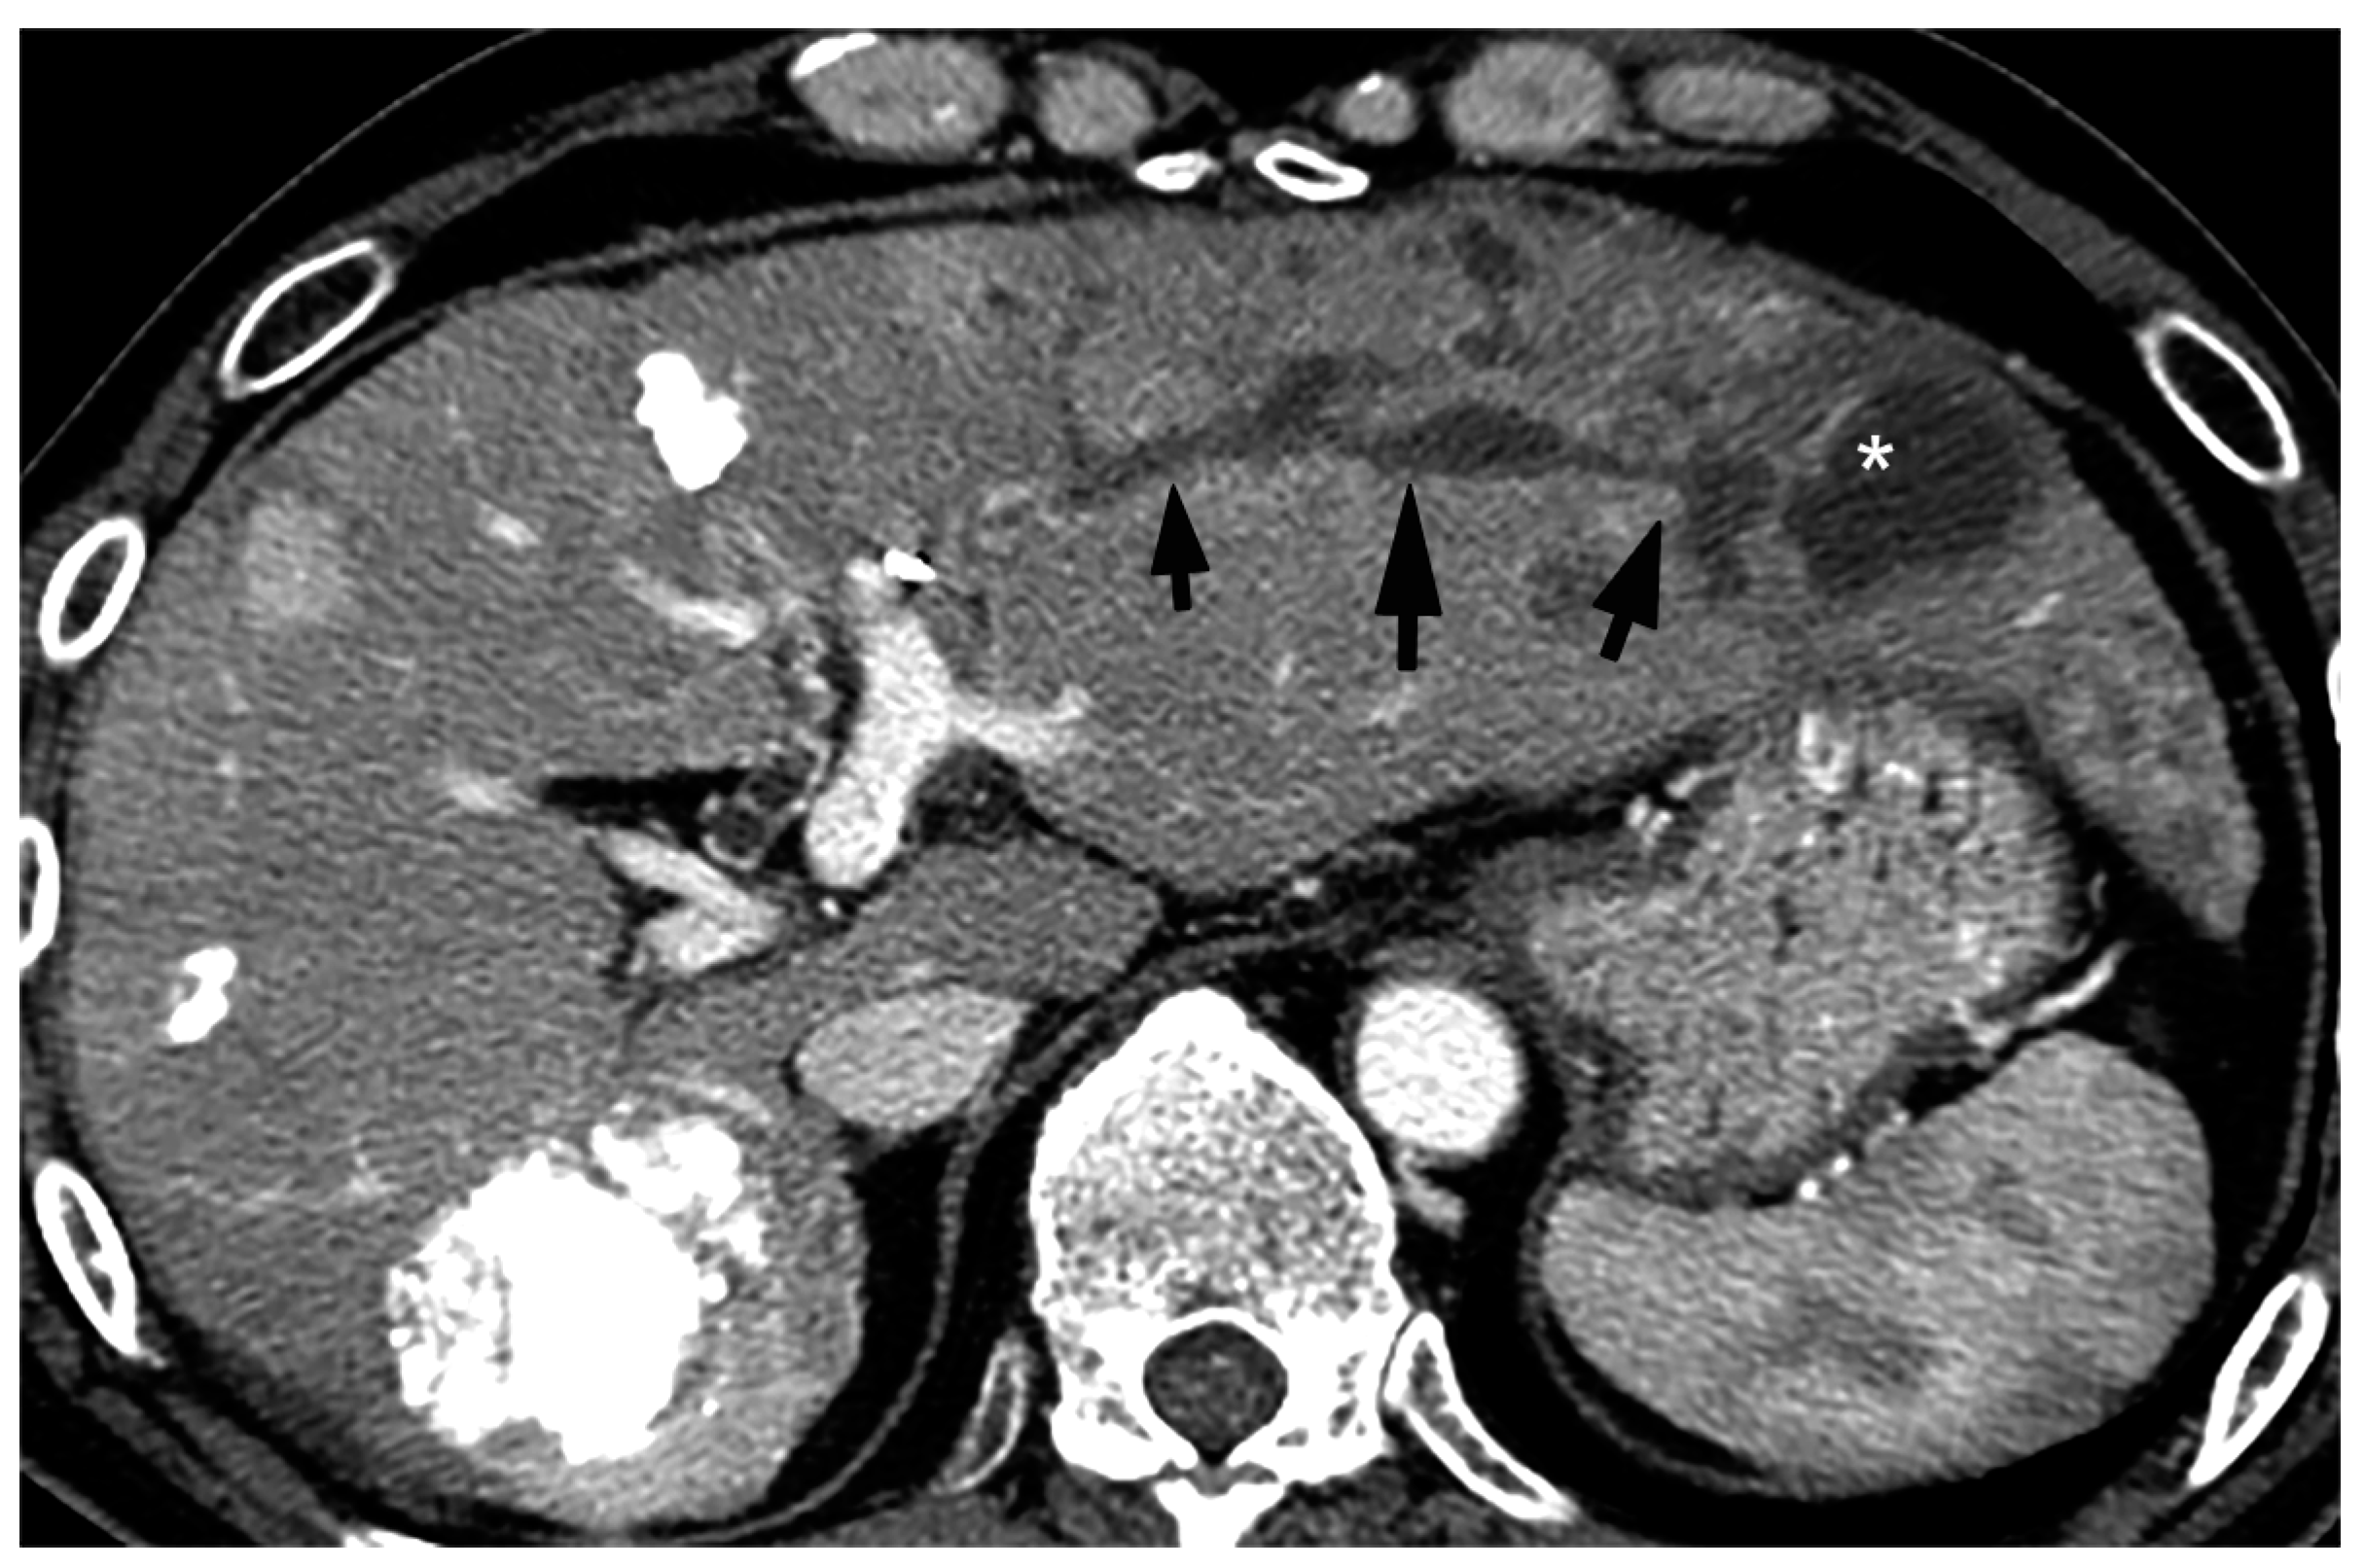

Figure 9. Portal phase image of contrast-enhanced CT of BDN and the biloma after transarterial therapy. A hypodense tubular structure (arrows) is connected to the large cystic lesion (*) in the lateral segment of the liver. The tubular structure is BDN of the anterolateral segment (S3) and the cystic lesion is biloma.

On pre-contrast and contrast-enhanced CT (CE-CT), BDN shows a linear hypodense structure along with a portal tract which looks like “intrahepatic bile duct dilatation” (Figure 9) [10,36]. The diameter of the lesion may show irregularity and might show findings similar to the “beaded-like appearance” observed in primary sclerosing cholangitis. Often, this finding is misdiagnosed as intrahepatic bile duct dilatation because the reason for the CT examination is a close examination of the cause of liver dysfunction, including increased serum bilirubin.

Figure 10. Equilibrium phase image of a contrast-enhanced CT of BDN. A hypodense tubular structure (arrows) is observed in the hepatic hilum of the right lobe. Enhancement of the right main portal branch is discontinued (*), which represents thrombotic obstruction of the portal vein caused by BDN. (Curved arrow is the biloma.).